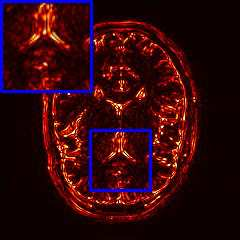

Limited by imaging systems, the reconstruction of Magnetic Resonance Imaging (MRI) images from partial measurement is essential to medical imaging research. Benefiting from the diverse and complementary information of multi-contrast MR images in different imaging modalities, multi-contrast Super-Resolution (SR) reconstruction is promising to yield SR images with higher quality. In the medical scenario, to fully visualize the lesion, radiologists are accustomed to zooming the MR images at arbitrary scales rather than using a fixed scale, as used by most MRI SR methods. In addition, existing multi-contrast MRI SR methods often require a fixed resolution for the reference image, which makes acquiring reference images difficult and imposes limitations on arbitrary scale SR tasks. To address these issues, we proposed an implicit neural representations based dual-arbitrary multi-contrast MRI super-resolution method, called Dual-ArbNet. First, we decouple the resolution of the target and reference images by a feature encoder, enabling the network to input target and reference images at arbitrary scales. Then, an implicit fusion decoder fuses the multi-contrast features and uses an Implicit Decoding Function~(IDF) to obtain the final MRI SR results. Furthermore, we introduce a curriculum learning strategy to train our network, which improves the generalization and performance of our Dual-ArbNet. Extensive experiments in two public MRI datasets demonstrate that our method outperforms state-of-the-art approaches under different scale factors and has great potential in clinical practice.